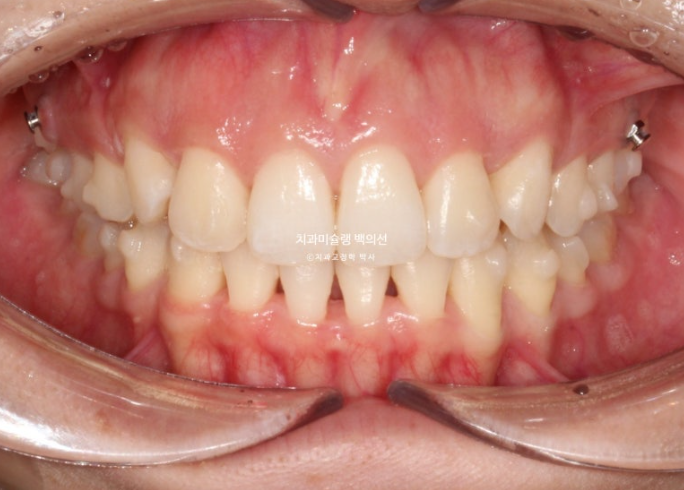

25.01

첫번째 추가장치를 모두 낀 후 모습입니다.

교합은 이미 1급 교합관계로 완성 상태입니다.

배열도 완벽합니다.

치료를 마무리 해도 되는 상황이나 환자분이 앞니 각도 개선을 좀 더 원하셔서 두번째 추가장치 제작에 들어갔습니다.

재제작 하는 김에 앞니 뿌리도 치조골 속으로 더 이동시켜서 잇몸건강 측면에서도 안정적인 결과를 도모합니다.

또한 아래 앞니 블랙트라이앵글 사이즈도 치간삭제를 통해 줄이기로 합니다.